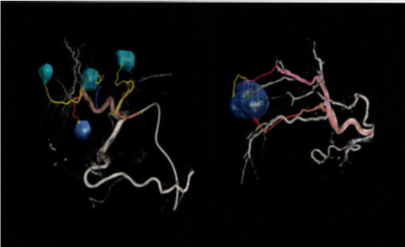

血管造影室

血管造影X線診断装置 Azurion7 B20/15

導入日2022.4

頭部・心臓をはじめ全身対応のフラットパネルバイプレーン血管造影装置です。

患者様に低侵襲治療をより安全に、より効率的に施行する事が可能な最新モデルです。主な特徴

- リアルタイム3D再構成機能

- 高速回転撮影中にリアルタイム3D再構成が可能で、撮影が終わると即時に3D画像が表示されます。さらにさまざまな計測・シミュレーション機能を搭載し、あらゆる手技を支援する機能です。

- ダイナミック3Dロードマッピング機能(SmartCT Roadmap)

- 血管3D像と透視画像とのフュージョンにより、3Dロードマップを可能とし低侵襲化を実現します。ロードマップはアームの回転・SIDや視野サイズの変更・寝台の移動だけでなく体動にも追従する動態補正機能を搭載し、多くの操作を自動化することで、よりスムーズかつ安全に手術を支援します。

- 栄養血管候補の描出/ナビゲーション機能(EmboGuide)

- 肝細胞癌に対するTACE(肝動脈化学塞栓療法)の際、得られた3D情報をもとに腫瘍に関わる栄養血管候補を描出し、複数の複雑で微細な塞栓ルート候補に対する治療戦略のシミュレーションを可能にします。